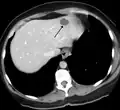

Liver

Infantile hemangiomas in the liver are found in 16% of all liver hemangiomas. Its sizes are usually less than 1 to 2 cm in diameter. It may show a "flash-filling" phenomenon in which there is a fast enhancement of the contrast material in the lesion instead of slow, centripetal, nodular filling of the lesions in usual hemangiomas. On CT and MRI, it shows rapid filling during arterial phase, with contrast retention in venous and delayed phases.[40]